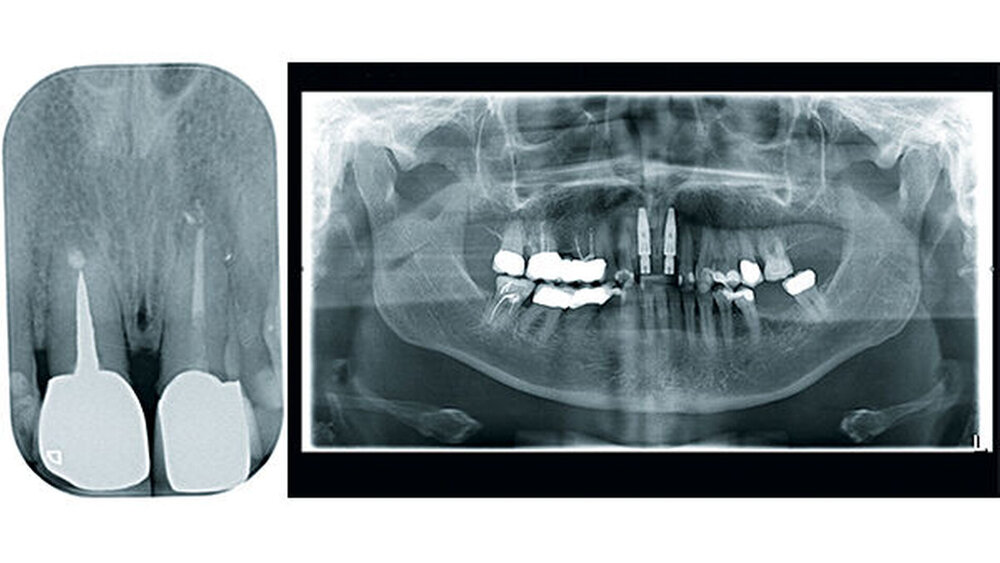

Infektionen der den Zahn umgebenden Gewebe führen infolge einer überschießenden Gewebereaktion zum Knochenabbau und im schlimmsten Fall zum Zahnverlust. Aufgrund der besonderen Situation der Perio-Integration von Implantaten und der ungenügenden Möglichkeiten der Dekontamination bakteriell belasteter Oberflächen ist ein präventiv-konzeptionelles Vorgehen notwendig. Transgingivale, möglichst einteilige Implantate entsprechen der Biologie des natürlichen Zahns eher als zweiteilige Implantate (Abb. 6, 7 und 8). Wir beobachten bei Keramikimplantaten zudem eine bessere Anlagerung der Weichgewebe.

Sofortimplantationen (auch mit Titanimplantaten) mit aus der Funktion genommenen Sofortversorgungen finden eine hohe Patientenakzeptanz, sind wirtschaftlich und aufgrund ihres biologischen Ansatzes weniger komplikationsbehaftet als aufwendige Augmentationen (Abb. 1a–1h). Insofern sollte eine Implantation bereits vor der Extraktion eines nicht erhaltungswürdigen Zahns geplant werden. Sicherlich ist es nicht möglich, den Bundle Bone, der eine Funktionseinheit des Zahnhalteapparats ist, nach einer Extraktion zu erhalten. Volumen und Dimension der Alveole und der den Zahn umgebenden Weichgewebe bleiben durch das Einbringen eines Implantats zu einem Großteil erhalten.

Das biologische, einteilig-transgingivale Implantat ist den mechanischen Einflüssen in der Mundhöhle ausgesetzt und benötigt bei geringer Primärstabilität (< 50 Ncm) unter Umständen eine zusätzliche Immobilisierung durch Verblockung mit den Nachbarzähnen oder Kronen. Der Scanner ist eine Möglichkeit der intraoperativen Abdrucknahme ohne die Gefahr der Inkontamination der Gewebesituation mit Abdruck- oder Provisorienmaterialien beziehungsweise der versehentlichen Inkorporation.

Zusätzlich kann das Emergenzprofil bereits intraoperativ in der Implantationssitzung gesteuert werden. Der Scan der ausgeheilten Situation vor der prothetischen Versorgung eröffnet die Möglichkeit, durch Einmatchen des Implantats in den Datensatz die subgingivale Situation zu simulieren ohne die Darstellung einer „Präparationsgrenze“ durch das Einlegen von Fäden. Diese Manipulationen sind traumatisch und zerstören die sensible hemidesmosomale Anhaftung der Gingiva- und Bindegewebsfasern an der Implantatoberfläche. Der digitale Abdruck wird die konventionelle Abformung in der modernen Zahnarztpraxis aufgrund seiner überlegenen Performance ersetzen. Den parodontologischen und minimalinvasiven Prinzipien folgend, ist die digitale Abformung von Zähnen auch in der ästhetisch sensiblen Zone angesichts der geringeren Traumatisierung der parodontalen Gewebe, der überragenden Präzision und der daraus folgenden Randpassung der Versorgung ein logischer und richtiger Weg in die Zukunft der zahnärztlichen Praxis (Abb. 10 – 14).